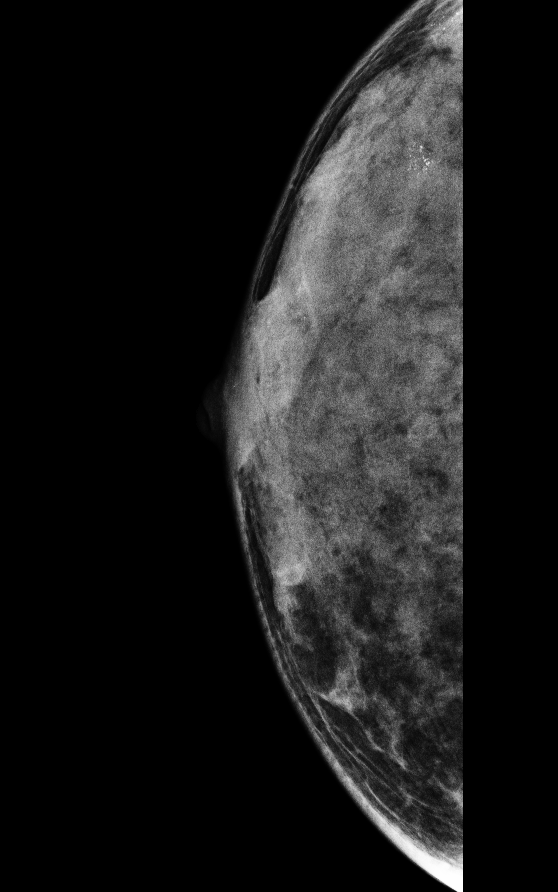

보통 유방 엑스레이 촬영을 할 때 지방이 많은 유방은 어둡게 보입니다. 그런데 치밀유방은 단단한 조직이 많아서 엑스레이 사진이 하얗게 나옵니다. 그런데 문제는 암과 같은 종양도 하얗게 보이기 때문에, 암이 있어도 잘 보이지 않을 수 있다는 점입니다. 그래서 치밀유방이 있는 사람들은 암을 찾기 어려울 수 있어서 주의가 필요합니다.

치밀유방은 유방 촬영(엑스레이) 사진에서 하얗게 보입니다. 그런데 암과 같은 종양도 하얗게 보이기 때문에, 두 개를 구별하기가 어렵습니다. 이는 마치 눈 덮인 들판에서 하얀 토끼를 찾는 것과 비슷합니다. 그래서 치밀유방이 있는 사람들은 암을 조기에 발견하기가 어려울 수 있습니다.

유방 촬영술은 여전히 기본적인 검진 방법입니다. 이 검사는 엑스레이를 사용해서 유방의 모습을 찍습니다. 하지만 치밀유방이 있는 경우 암 발견이 어려울 수 있으므로 추가적인 검사를 함께 하는 것이 좋습니다.